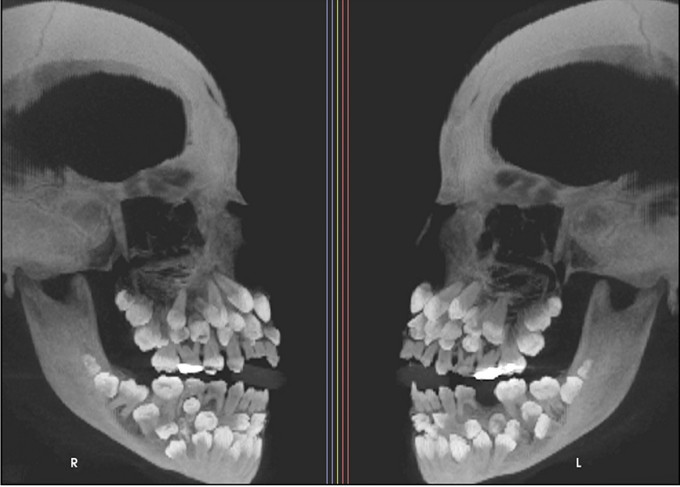

Tuy nhiên, kết quả chụp X-quang cho thấy một phát hiện gây sốc, thực tế bé có 18 răng sữa, 32 răng vĩnh viễn và 31 răng thừa, tổng cộng là 81 răng.

Khi khám răng, bác sĩ nhận thấy chỉ có 5 răng vĩnh viễn đã mọc, trong khi vẫn còn khá nhiều răng sữa. Để đánh giá toàn diện hơn tình trạng răng miệng của bé, bác sĩ đã chỉ định chụp X-quang tổng quát và chụp sọ nghiêng.

Những hình ảnh cho thấy nhiều răng bị biến dạng và nằm sâu trong nướu, khiến việc phân biệt giữa răng bình thường và răng thừa rất khó khăn. Trung bình, một người trưởng thành có 32 chiếc răng và những chiếc răng thừa này được gọi là "siêu răng". Thông thường, chỉ có 1 hoặc 2 chiếc răng thừa.